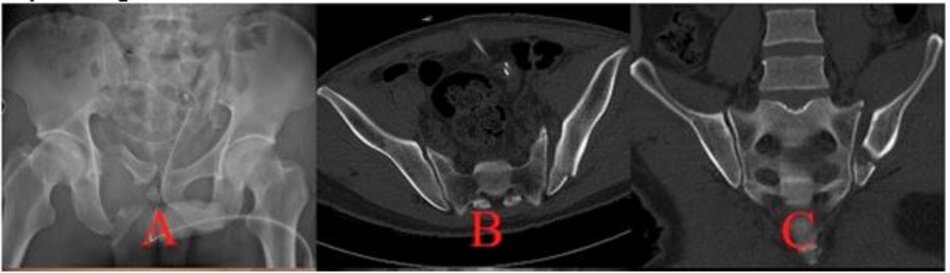

Phẫu thuật Vỡ xương chậu phức tạp

Phẫu thuật đường trước:

Hình ảnh vỡ xương chậu phức tạp

Hình ảnh đường mổ và phim chụp sau mổ đạt kết quả đúng giải phẫu